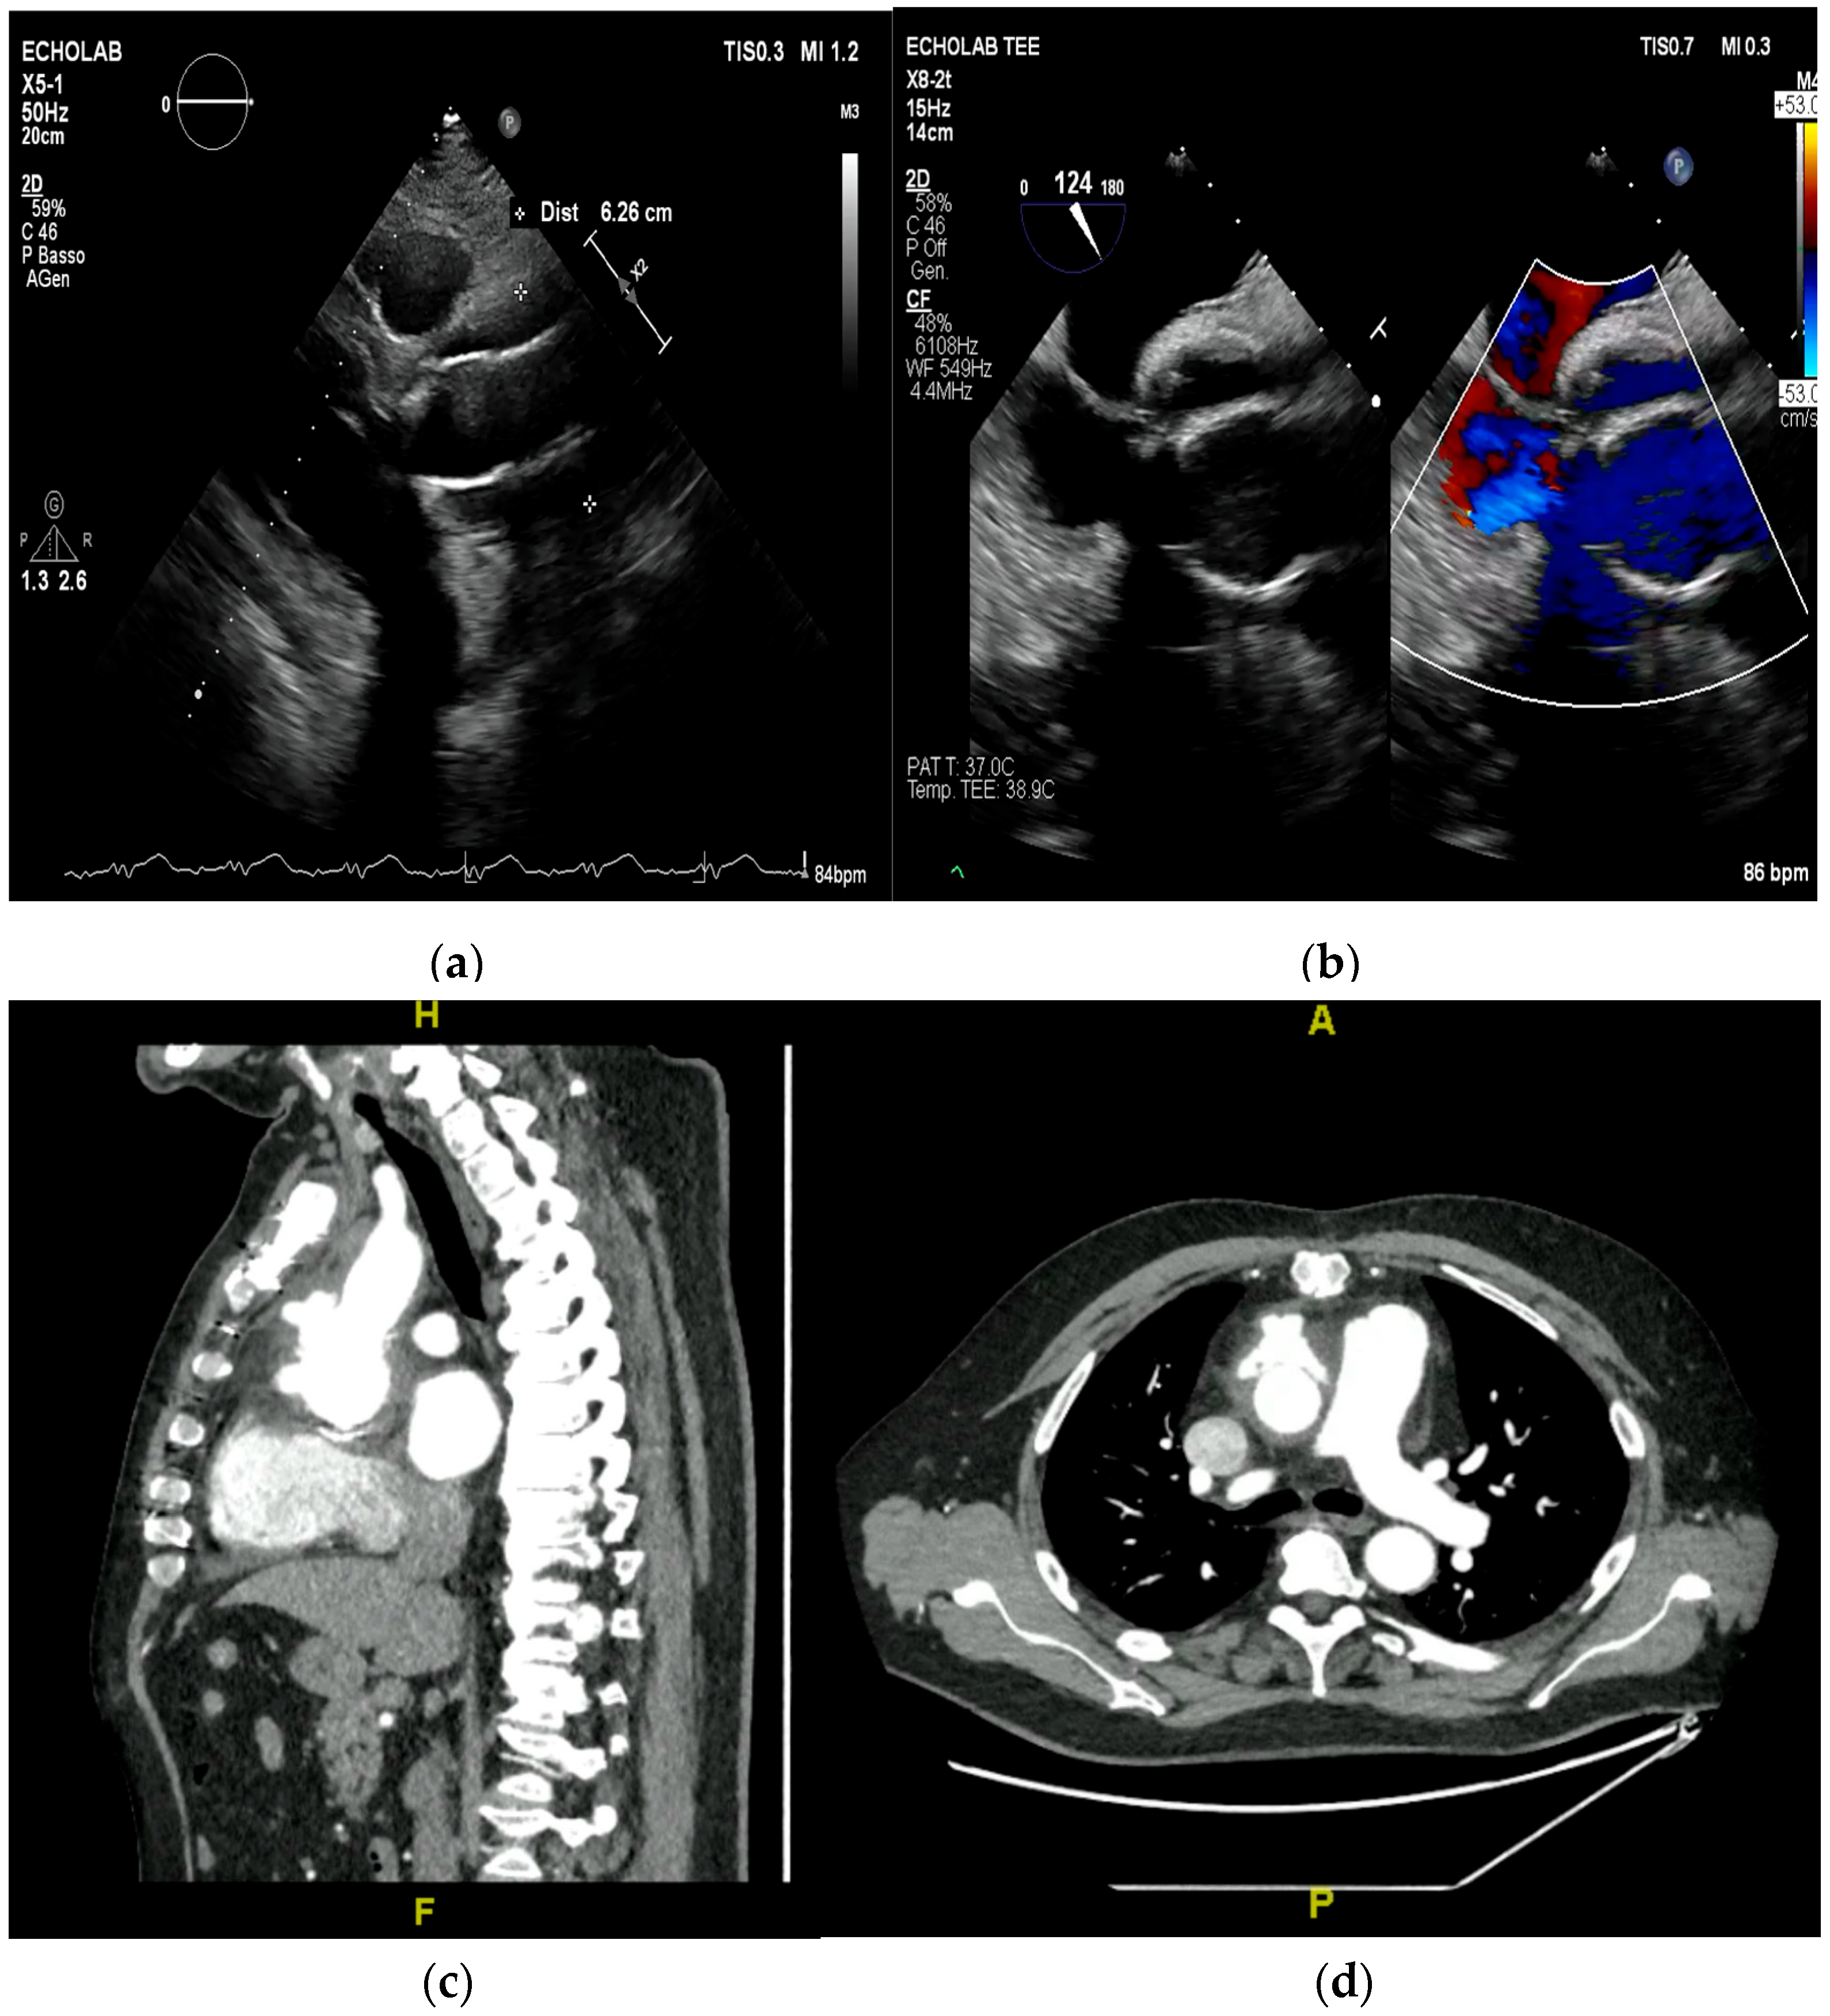

5. Cardiac Computed Tomography

- vs. Cardiac CT: Cardiac CT is superior for detailed anatomical delineation of paravalvular structures, calcifications, and pseudoaneurysms due to its higher spatial resolution. It is the preferred modality for pre-surgical coronary angiography. CMR, however, provides superior soft-tissue characterization (differentiating edema, necrosis, and thrombus) and functional data without radiation [17,38].

- Cardiac CT: While excellent for anatomical definition, cardiac CT has limited sensitivity for small (<10 mm) mobile vegetations and cannot assess hemodynamic status. Its use is also limited by radiation exposure and the need for a stable sinus rhythm for accurate electrocardiographic gating, as arrhythmias can degrade image resolution and diagnostic yield [37,60,61]. Additionally, the use of iodinated contrast media carries a risk of nephrotoxicity, a relevant concern in a patient population often affected by chronic kidney disease.